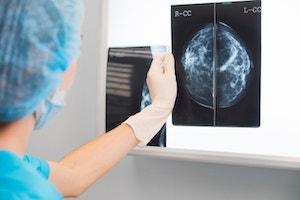

While some men and women experience symptoms, many breast cancer patients show no symptoms. That is why early detection, testing, and screening is so important. Common screening tools include mammograms, breast ultrasounds, breast MRI Scans, and new breast imaging. Some patients also receive a breast biopsy (fine-needle aspiration biopsy, large-core biopsy, or open surgical biopsy).